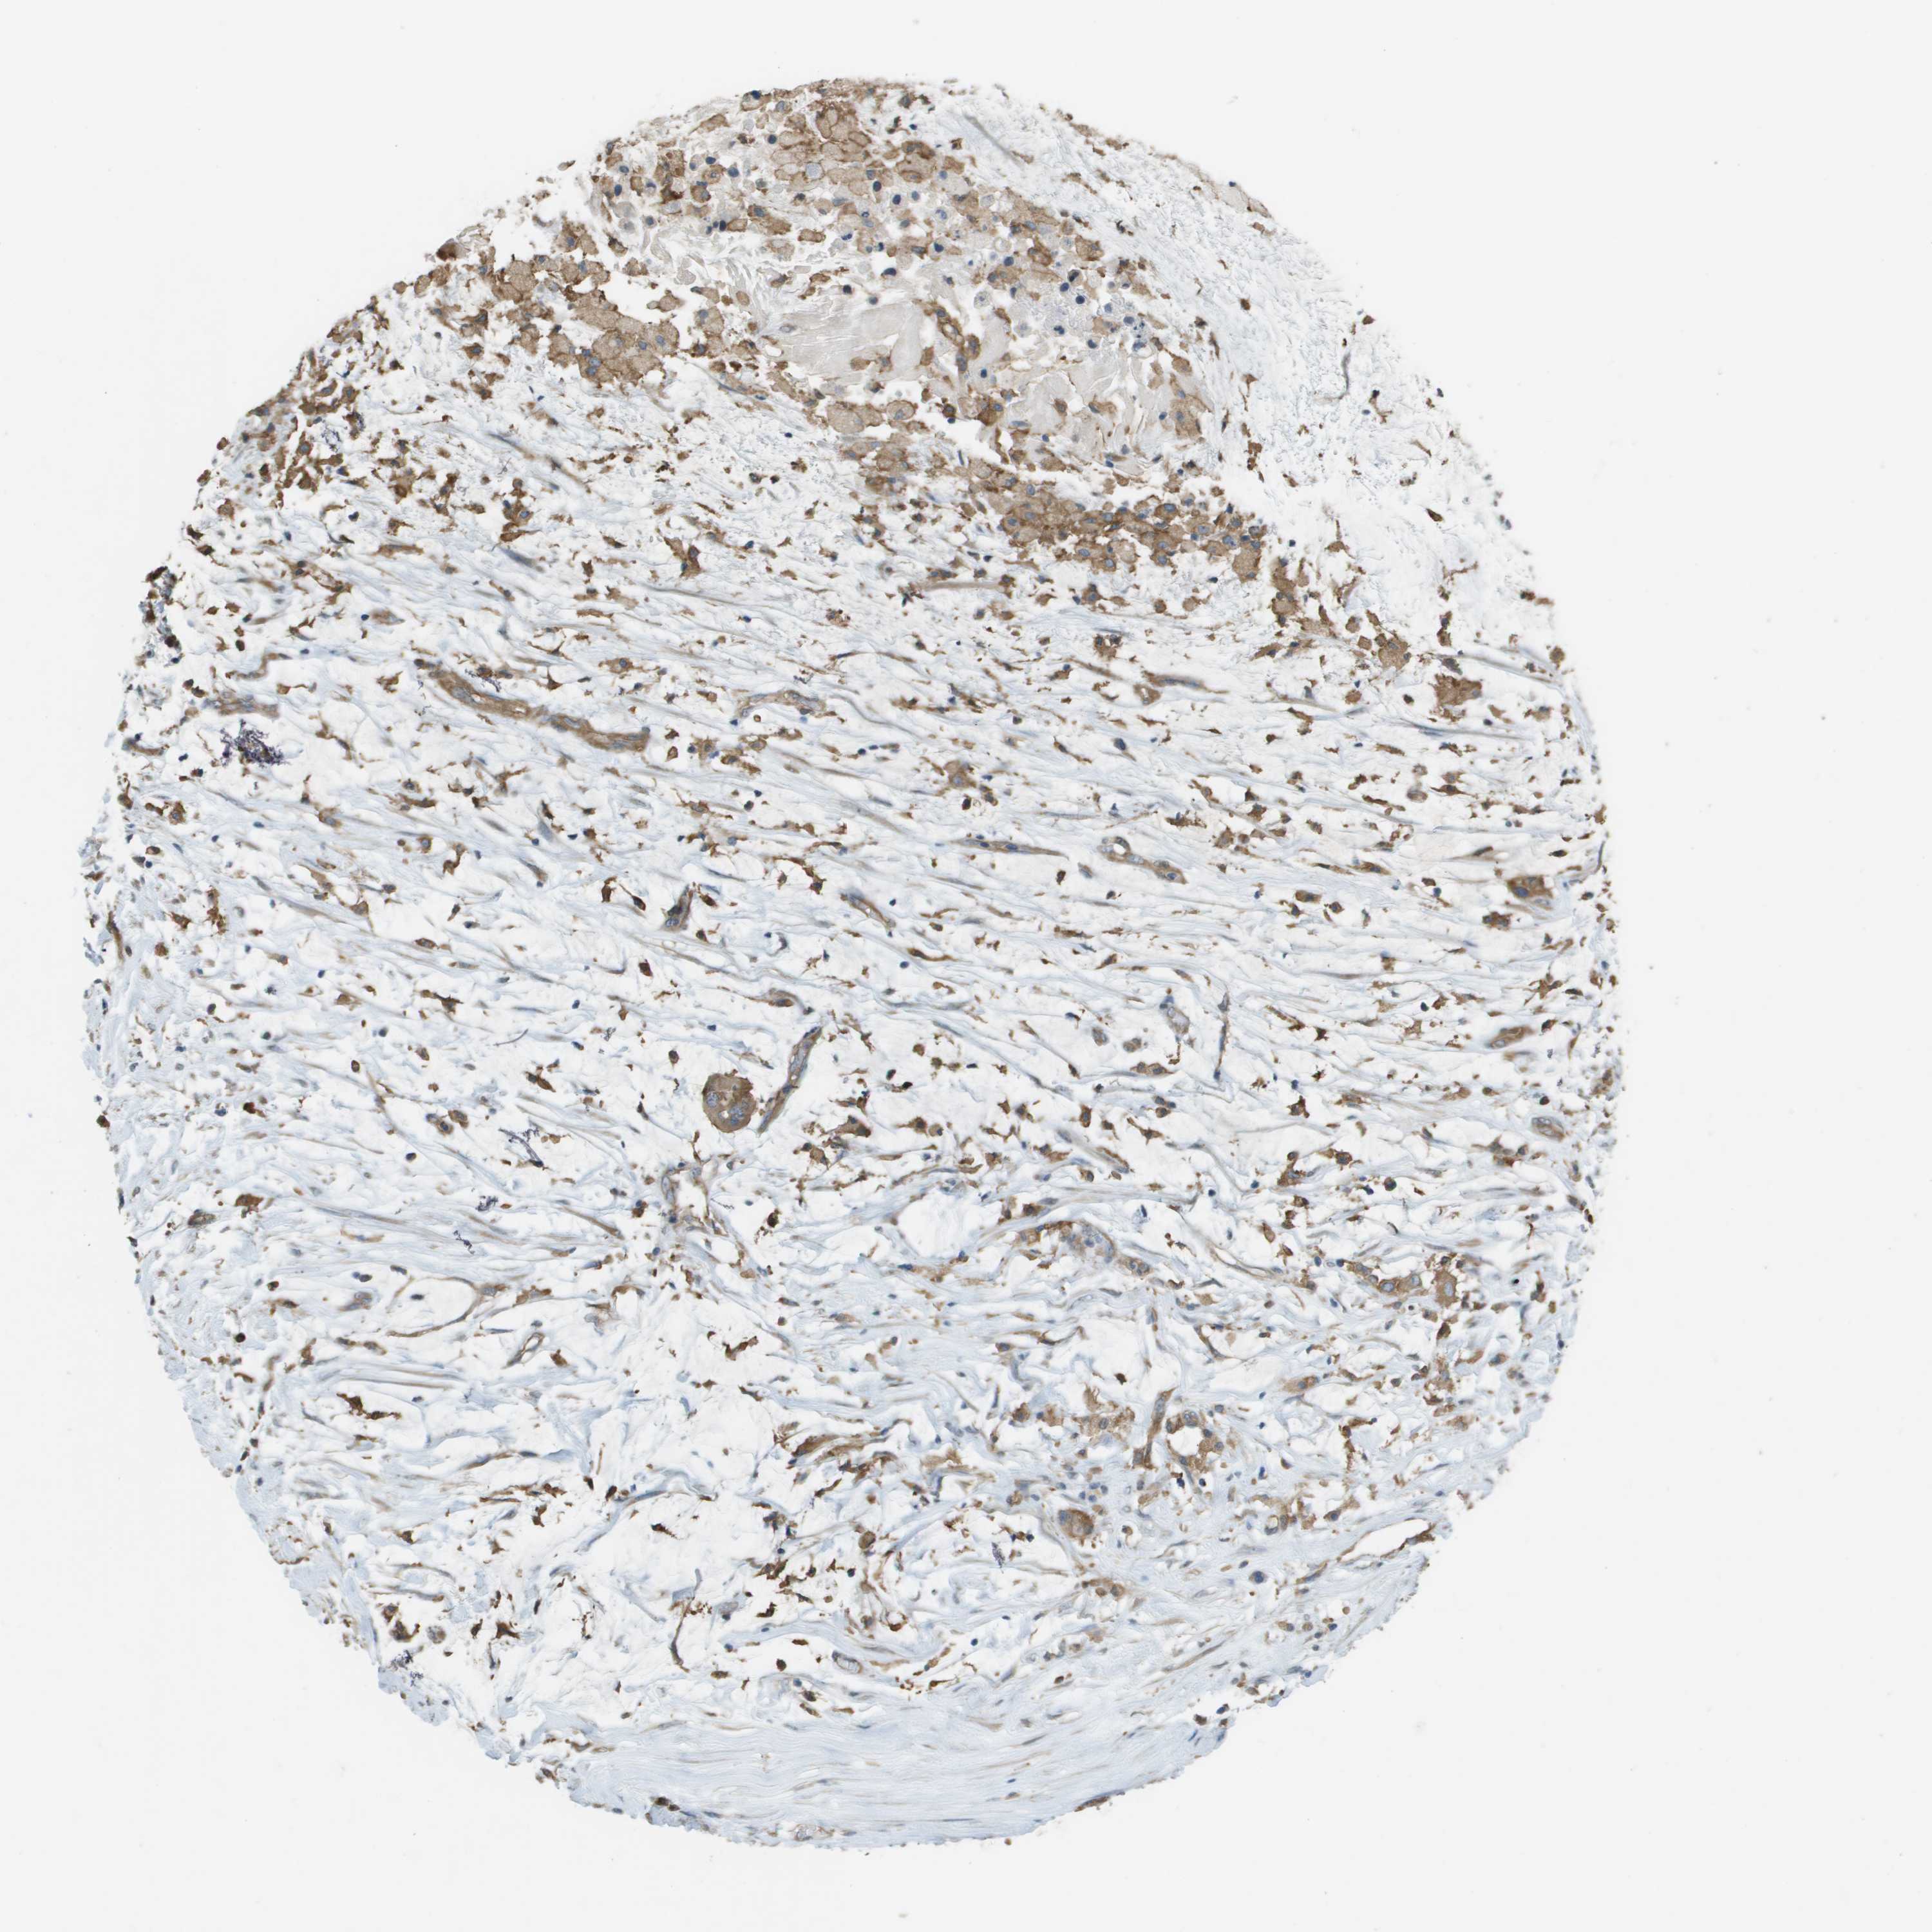

OVARIAN CANCER - Protein expressioni

A mouse-over function shows sample information and annotation data. Click on an image to view it in a full screen mode. Samples can be filtered based on level of antibody staining by selecting one or several of the following categories: high, medium, low and not detected. The assay and annotation is described here.

Note that samples used for immunohistochemistry by the Human Protein Atlas do not correspond to samples in the TCGA dataset.

Antibody stainingi

Antibody staining in the annotated cell types in the current human tissue is reported as not detected, low, medium, or high, based on conventional immunohistochemistry profiling in selected tissues. This score is based on the combination of the staining intensity and fraction of stained cells.

Each image is clickable and will lead to virtual microscopy that enables deeper exploration of all samples and also displays staining intensity scores, fraction scores and subcellular localization as well as patient and tissue information for each sample.

Antibody HPA070456

Antibody CAB017616

Staining

High

Medium

Low

Not detected

Intensity

Strong

Moderate

Weak

Negative

Quantity

>75%

75%-25%

<25%

None

Location

Nuclear

Cytoplasmic/membranous

Cytoplasmic/membranous,nuclear

Cystadenocarcinoma, serous, NOS

Cystadenocarcinoma, mucinous, NOS

Carcinoma, endometroid

Carcinoma, NOS